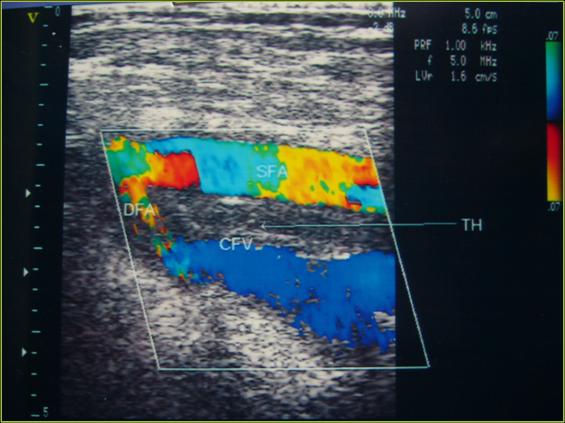

考虑患者肺部栓塞部位及范围,以及术后不足24小时,存在出血可能,未给予RT-PA溶栓,积极吸氧,积极低分子肝素抗凝,解痉,扩容,监测凝血机能。复查D-二聚体依然阴性,FIB656mg/ml。三天后病情平稳,于2.21行双下肢多普勒检查,提示右股总静脉及股深静脉血栓,给予尿激酶治疗。3.2复查胸部CT,原肺部实变区域消失。随即复查双下肢多普勒依然可见血栓,复查左上臂X光片,固定愈合良好。3.21再次复查血栓再通,患者康复出院。

多篇文献报道,彩色多普勒检测敏感性大约92-95%,特异性97-100%,准确性92%。应用彩色多普勒诊断下肢深静脉血栓形成准确、快捷、经济、方便、可重复,并对临床治疗有一定的指导意义,是一种无创的、有效的检查方法,与血管检查金标准“血管造影”差异不大,主要受医师经验及检查水平影响。